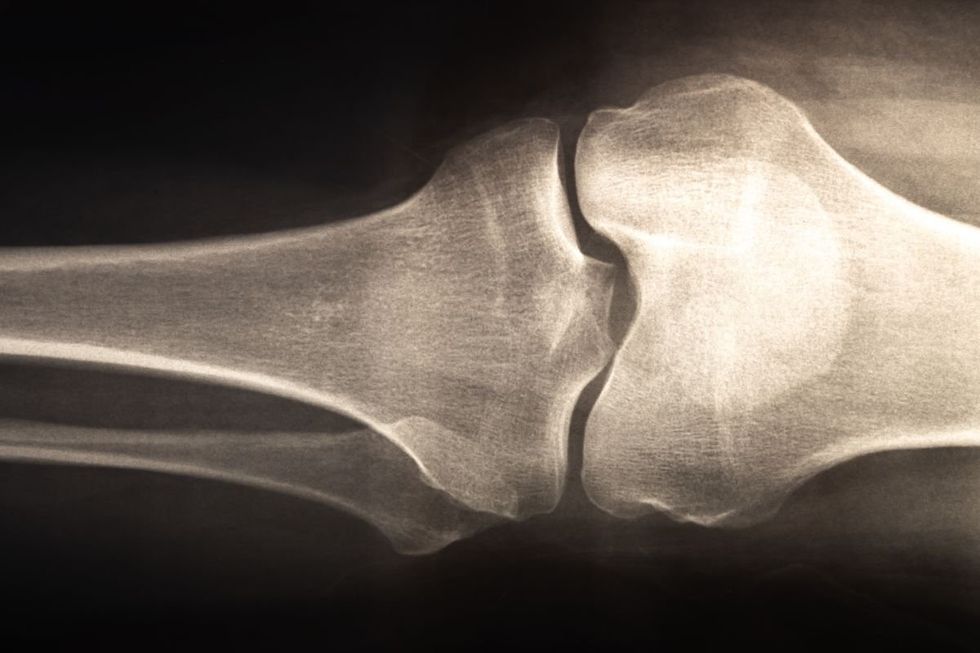

Following a Mediterranean diet can substantially reduce the likelihood of suffering hip fractures and other bone breaks, according to a new analysis from the University of Chester.

Their findings, published in the journal Nutrients, demonstrate while different dietary approaches had minimal effect on bone mineral density, those adhering to Mediterranean eating patterns experienced notably fewer fractures.

The study outlines how the Mediterranean diet's protective qualities stem from its rich combination of nutrient-dense foods.

Dr Kanakis continued: "Plausible reasons for the findings on the Mediterranean diet include higher intakes of fruits, vegetables, whole grains, legumes, fish, and olive oil that collectively supply calcium, magnesium, vitamin K, potassium, polyphenols (natural compounds found in plants), and anti-inflammatory constituents supportive of bone remodelling and microarchitecture."

The research underscored that nutrition influences skeletal health through multiple pathways extending beyond individual nutrients such as calcium, vitamin D and protein.

Rather, overall dietary patterns integrate a broad spectrum of bioactive compounds and macronutrient interactions that collectively determine musculoskeletal outcomes.